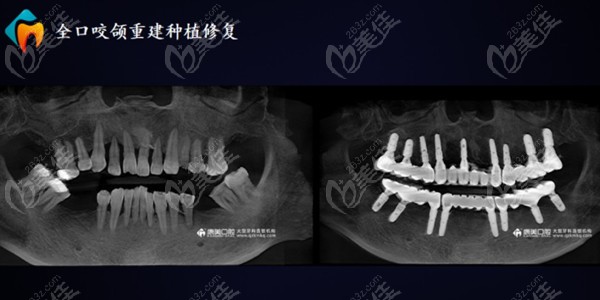

钦州康美口腔种植牙技术还蛮好,廖勇医生的种牙病例数将近上万例 b696 G0 V0

听说钦州康美口腔廖勇医生的种植牙病例数量将近有上万例,那你还问钦州康美口腔种植牙好不好吗?难道好的种植医生不能说明什么吗?